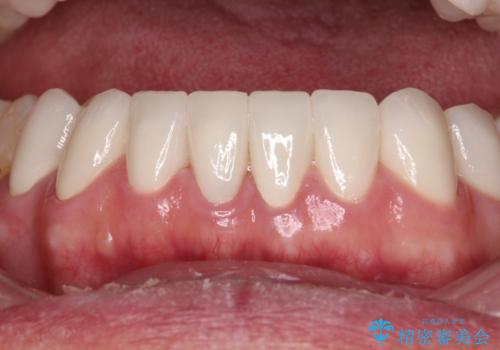

憧れの白い歯に 全顎セラミック治療

- 60歳を越え、黄ばんだ前歯をセラミッククラウンできれいな口元にしたいとのことで来院された患者様です。

診察したところ、前歯は反対咬合であり、その影響で抜歯が必要な奥歯があることが分かりました。

抜歯が必要な奥歯は、インプラント並びにブリッジにより補綴を行い、上下前歯は反対咬合を改善させるように補綴治療を行うこととしました。

健全な歯を削ってセラミッククラウンに置き換えることは、本来避けるべき治療と考えますが、今回は①患者様が60歳を越えていること、②要改善の咬合により抜歯が必要な奥歯があること、③反対咬合の前歯改善の手段としてセラミック治療が選択肢にあることなどから、全顎的なセラミック治療を行うこととしました。